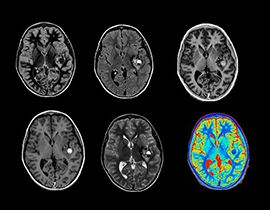

Das Geheimnis von MAGiC liegt in seiner einzigartigen Fähigkeit, mehrere Bildkontraste in nur einem Scan zu ermöglichen. MAGiC bewirkt eine höhere klinische Flexibilität, weil es Zeit für eine fortgeschrittene Bildgebung freisetzt. MAGiC stellt ergänzende parametrische Daten zugunsten eines vollständigeren Bildes bereit und geht damit über den Standard hinaus. Der Bildkontrast kann durch einfache Anpassungen nach der Aufnahme geändert werden.

NeuroQuant

NeuroQuant segmentiert und misst automatisch die Volumen von Hirnstrukturen und vergleicht diese Volumen mit Normwerten. Anhand solcher Informationen unterstützt es die Diagnosestellung und die Beobachtung des Krankheitsverlaufs. NeuroQuant stellte Bericht zu einer Vielzahl klinischer Aspekte bereit, darunter zu altersbedingter Atrophie, Hippocampus-Volumenasymmetrie, Atrophie mehrerer Strukturen, Triage der Hirnatrophie, Gehirnentwicklung und allgemeiner Morphometrie.